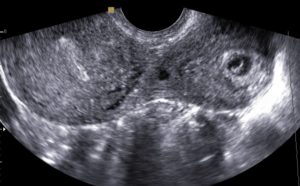

Прогрессирующая беременность – это беременность, которая развивается и малыш соответствует физиологическим нормам. То есть его развитие происходит согласно установленному «плану» природы.

Для прогрессирующей маточной беременности характерны следующие признаки.

На ранних сроках:

Симптомы ранней маточной беременностью идентичны с патологической внематочной гестации. Различить их можно в комплексе с лабораторными анализами и ультразвуковым исследованием.

Внематочная беременность – угрожающее состояние для здоровья и жизни  женщины.

Прогрессирующая беременность, развивающаяся в маточной полости подтверждается результатами УЗИ – трансабдоминальное и вагинальное. Вагинальный способ применяется на сроке не более 10 недель.

УЗ диагностика стопроцентно подтверждает, прогрессирует ли беременность, и к какому виду она принадлежит.

Исследование позволяет также выявить аномальное развитие плода на ранних сроках.